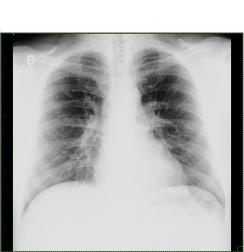

Radiografie